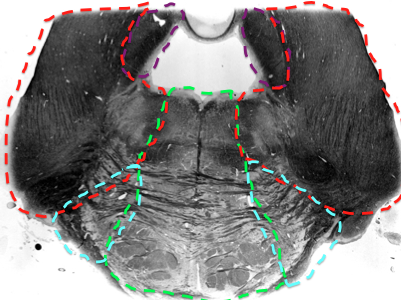

What supplies blood to the pons?

What features in the pons do the (paramedian) basilar branches supply blood to?

What features in the pons do the superior cerebellar artery supply blood to?

trochlear nerve

superior cerebellar peduncle

locus coeruleus

mesecenphalic trigem n.

some medial lemniscus

ALS

What features in the pons does AICA supply blood to?

middle cerebellar peduncle